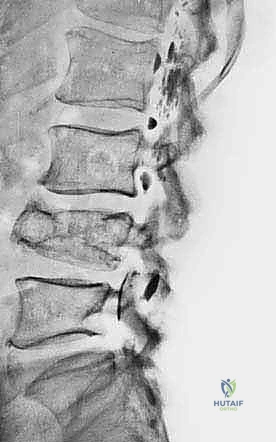

- الأشعة السينية (X-ray): الخطوة الأولى لتقييم العظام وتحديد نمط التدمير العظمي.

- الرنين المغناطيسي (MRI): هو المعيار الذهبي (Gold Standard) لتقييم الأورام. يوضح بدقة امتداد الورم في النخاع العظمي والأنسجة الرخوة، وعلاقته بالأعصاب والأوعية الدموية.

- الأشعة المقطعية (CT Scan): ضرورية لتقييم القشرة العظمية والتكلسات داخل الورم، وللبحث عن أي انتشار في الرئتين.

يعتمد الأستاذ الدكتور محمد هطيف على دراسة هذه الصور الإشعاعية شخصياً قبل تحديد مسار إبرة الخزعة، لضمان عدم تلويث الحجرات العضلية السليمة (Compartments).